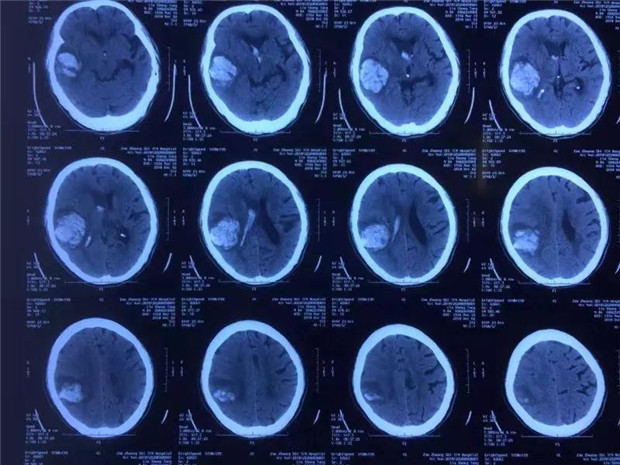

近日,我院神经外科接诊一位84岁高血压性脑出血老人。病人入院后已经昏迷,肢体瘫痪,随即出现脑疝。颅脑CT显示右侧颞、顶叶出血并形成占位性血肿,同时血肿破入脑室系统,估算出血量约70毫升。

患者术前脑CT